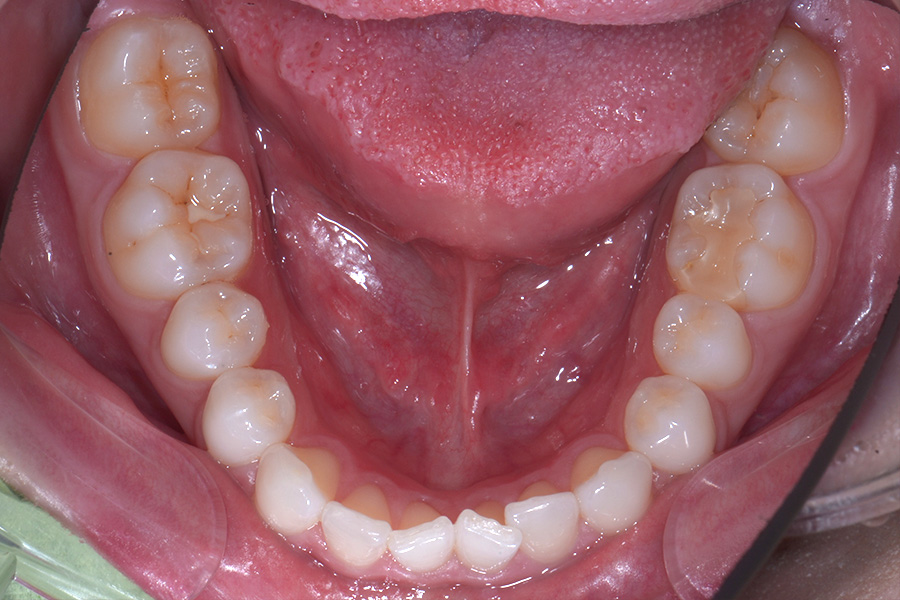

【20代女性】

前歯のすきっ歯と

捻じれを治したい

治療前

主訴 前歯のすきっ歯と捻じれを治したい

期間 8か月

費用 40万円(別途調整料)

治療内容 上下顎ラビアル矯正(表側矯正)